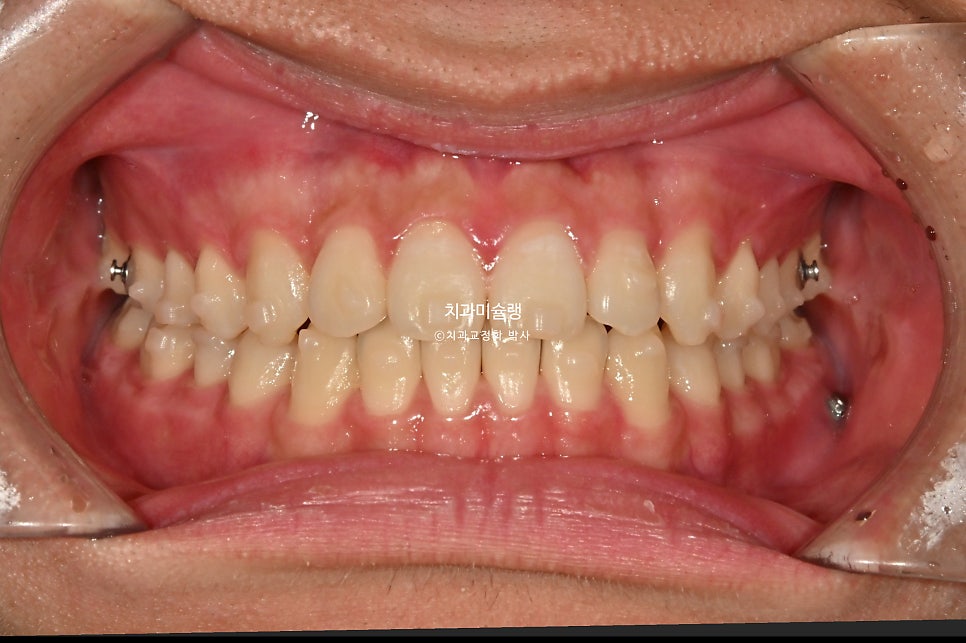

다시 가을학기를 위해 출국하여2025년 12월, 겨울방학때 46번 장치를 끼던 당시 내원한 모습입니다.

앞니 교합은 좋아졌으며 중심선이 약간 아쉽습니다.

우측 교합관계는 1급을 달성했으나 좌측 교합관계가 아직 아쉽습니다.

장치가 약 4개 남은 상태라 고무줄을 최대한 열심히 끼기로 하고 다시 출국, 2026년 3월 봄방학때 50번 마지막 장치를 마지막으로 치료를 종료했습니다.